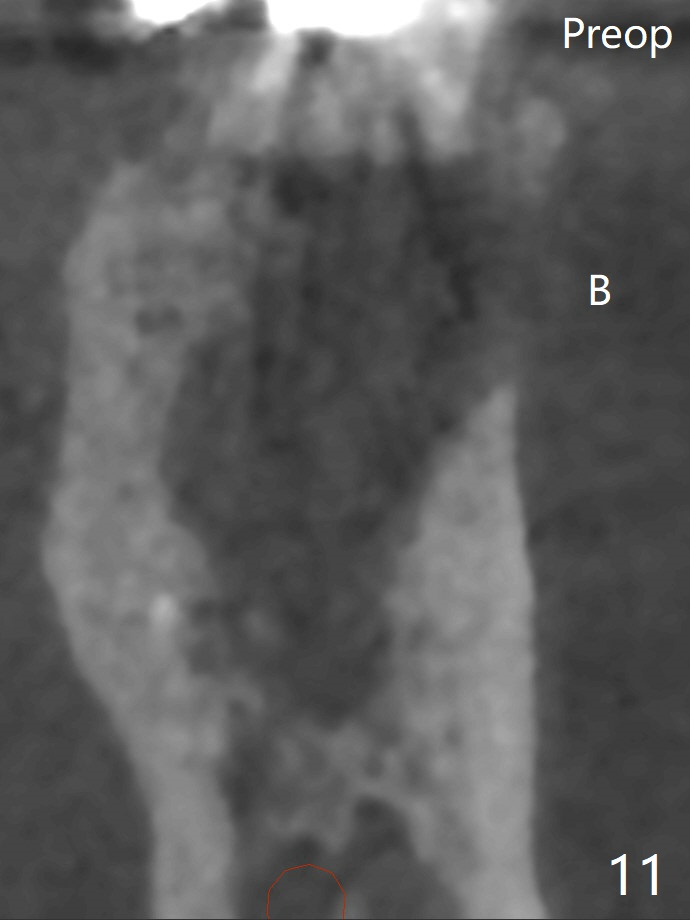

Bone Density Post Extraction with or without Bone Graft

10 Months Upper Molar